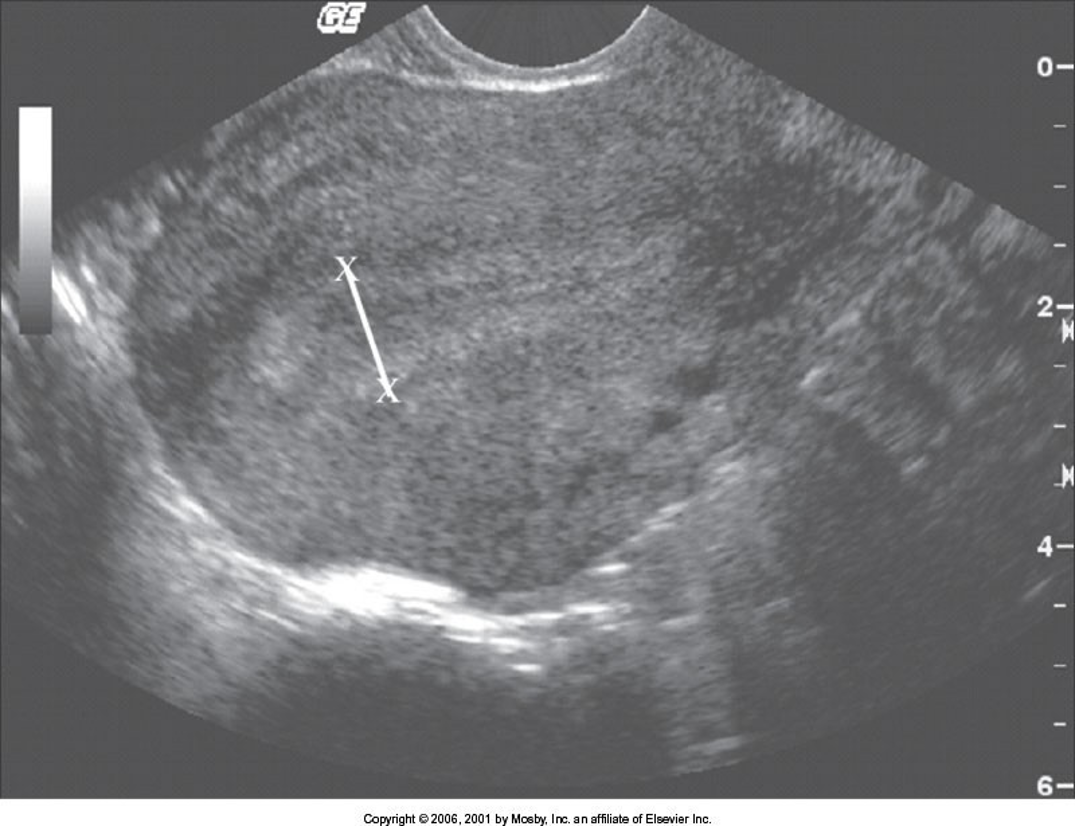

assess thickness and echogenicity pattern

increased thickness 2-3 mm –> 12-14 mm

measuring endometrium